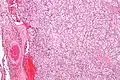

| Micrograph of a carotid body tumor (a type of paraganglioma). | |

On microscopic inspection, the tumor cells are readily recognized. Individual tumor cells are polygonal to oval and are arranged in distinctive cell balls, called Zellballen.[8] These cell balls are separated by fibrovascular stroma and surrounded by sustentacular cells.

By light microscopy, the differential diagnosis includes related neuroendocrine tumors, such as carcinoid tumor, neuroendocrine carcinoma, and medullary carcinoma of the thyroid.

With immunohistochemistry, the chief cells located in the cell balls are positive for chromogranin, synaptophysin, neuron specific enolase, serotonin, neurofilament and Neural cell adhesion molecule; they are S-100 protein negative. The sustentacular cells are S-100 positive and focally positive for glial fibrillary acidic protein. By histochemistry, the paraganglioma cells are argyrophilic, periodic acid Schiff negative, mucicarmine negative, and argentaffin negative.

Micrograph of a carotid body tumor